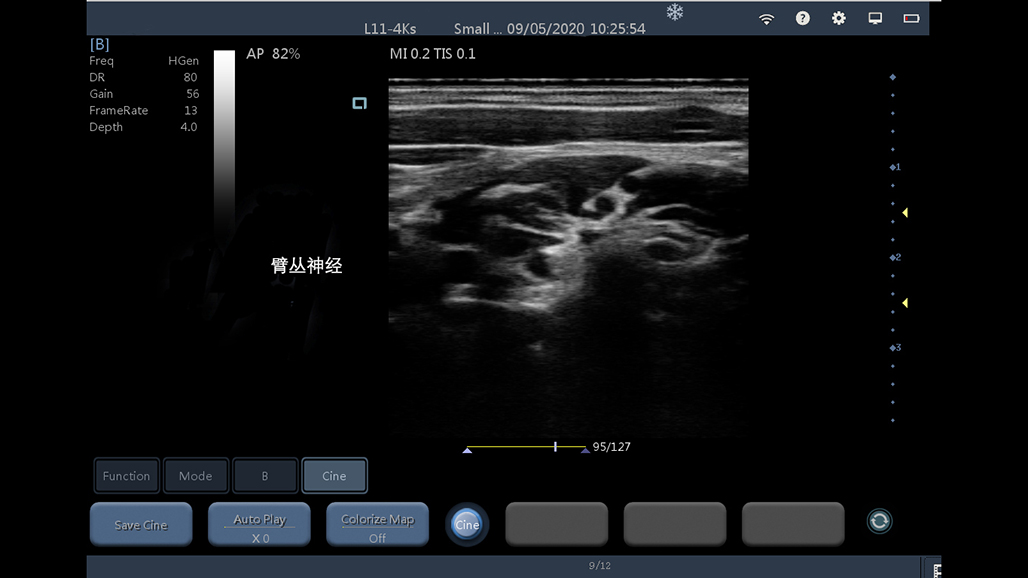

• 线阵

神经